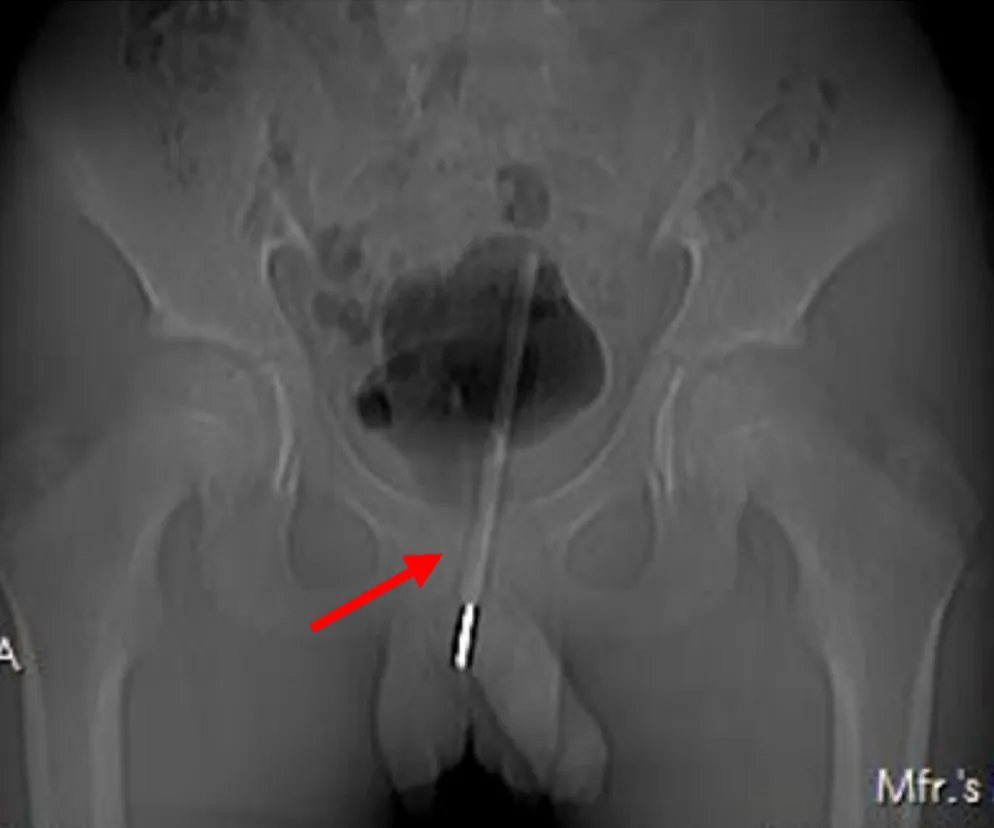

Nastolatek z Chin wymagał pilnej pomocy medycznej. Chłopak został przewieziony do szpitala. 12-latek przez dziewięć godzin chodził z termometrem w cewce moczowej. Ból podbrzusza wywołany urządzeniem medycznym był nie do zniesienia. Lekarze obawiali się, że wyciągnięcie go przez prącie może uszkodzić ten narząd. Postanowiono więc położyć chłopaka na stole operacyjnym.

Jak czytamy w udostępnionym przez lekarzy raporcie, medycy postanowili przeprowadzić na 12-latku operację. Nie chcieli wyciągać medycznego urządzenia przez prącie z obawy o jego uszkodzenie. Urolodzy zrobili więc niewielki otwór w pęcherzu moczowym, a następnie włożyli do jego wnętrza specjalne narzędzie, którym ustawili termometr pod odpowiednim kątem. Kiedy przedmiot znalazł się w określonej pozycji, dzięki laparoskopii udało się lekarzom go chwycić i wyciągnąć na zewnątrz pacjenta.